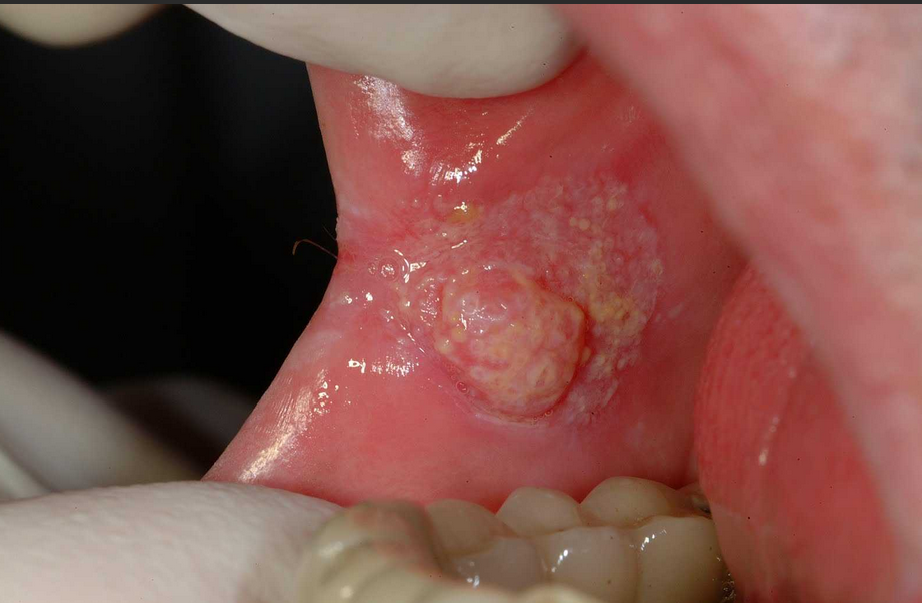

Verrucous Carcinoma

A slow-growing variant of squamous cell carcinoma that rarely spreads but can be locally aggressive.

Persistent Mouth Sores

Sores that don't heal within 2 weeks or keep recurring in the same location.

White or Red Patches

Leukoplakia (white) or erythroplakia (red) patches that cannot be scraped off.

Lump or Thickening

Any lump, thickening, rough spot, or eroded area in the mouth.